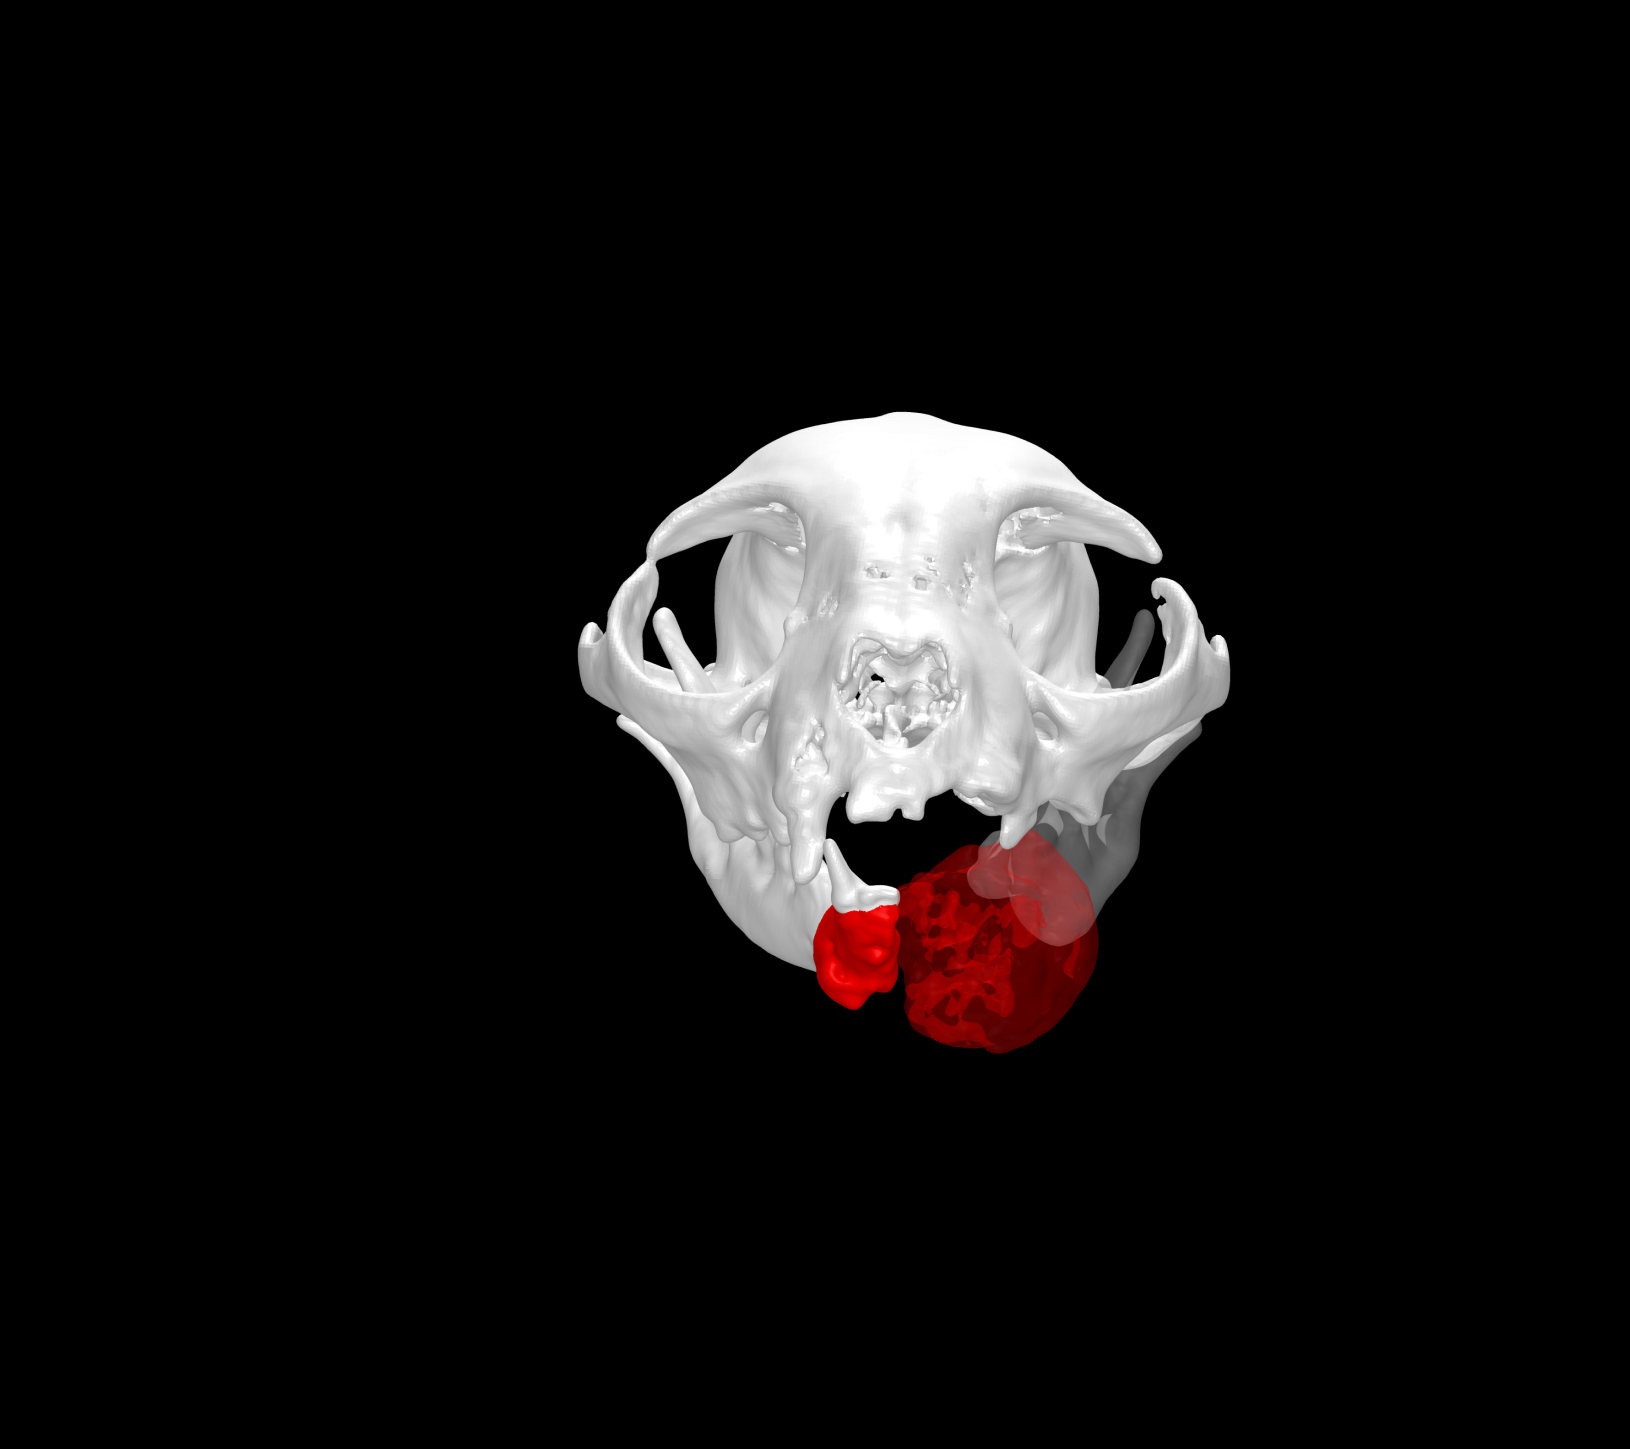

Esto se consigue gracias a los avances en la tecnología de fabricación, como la impresión 3D. Con esta tecnología se pueden crear implantes personalizados tanto en acero quirúrgico como en titanio a partir de imágenes médicas de tomografías computerizadas (TC) o resonancias magnéticas (RM).

- Mejor ajuste y adaptación al paciente: favorece la colocación precisa y la estabilidad del implante sobre la anatomía quirúrgica.